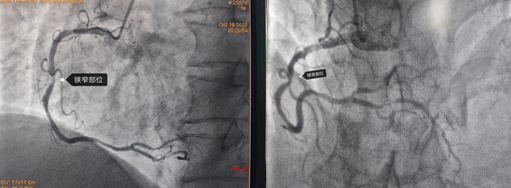

2021年10月19日,64歲的馬先生因胸悶、心悸等癥狀入住心血管九病區(qū),馬先生有高血壓、吸煙等冠心病危險(xiǎn)因素,心電圖有心肌缺血表現(xiàn),為明確馬先生是否為冠心病所致上述癥狀以及決定下一步診治方案,給他進(jìn)行了冠脈造影檢查,結(jié)果如下圖:

造影結(jié)果右冠多處狹窄約70-90%,左冠也是多處70-80%狹窄;對于這樣一個結(jié)果,是這些狹窄造成的胸悶、心悸嗎?這些病變需不需要都給予介入處理呢?一根血管植入支架還是三根血管都需要植入支架?心內(nèi)九科崔旭輝主任帶領(lǐng)介入醫(yī)生團(tuán)隊(duì)討論后,決定進(jìn)行RFR檢查給出一個明確的答案。所以經(jīng)過與患者及其家屬溝通后選擇進(jìn)行RFR檢測,結(jié)果如下圖: